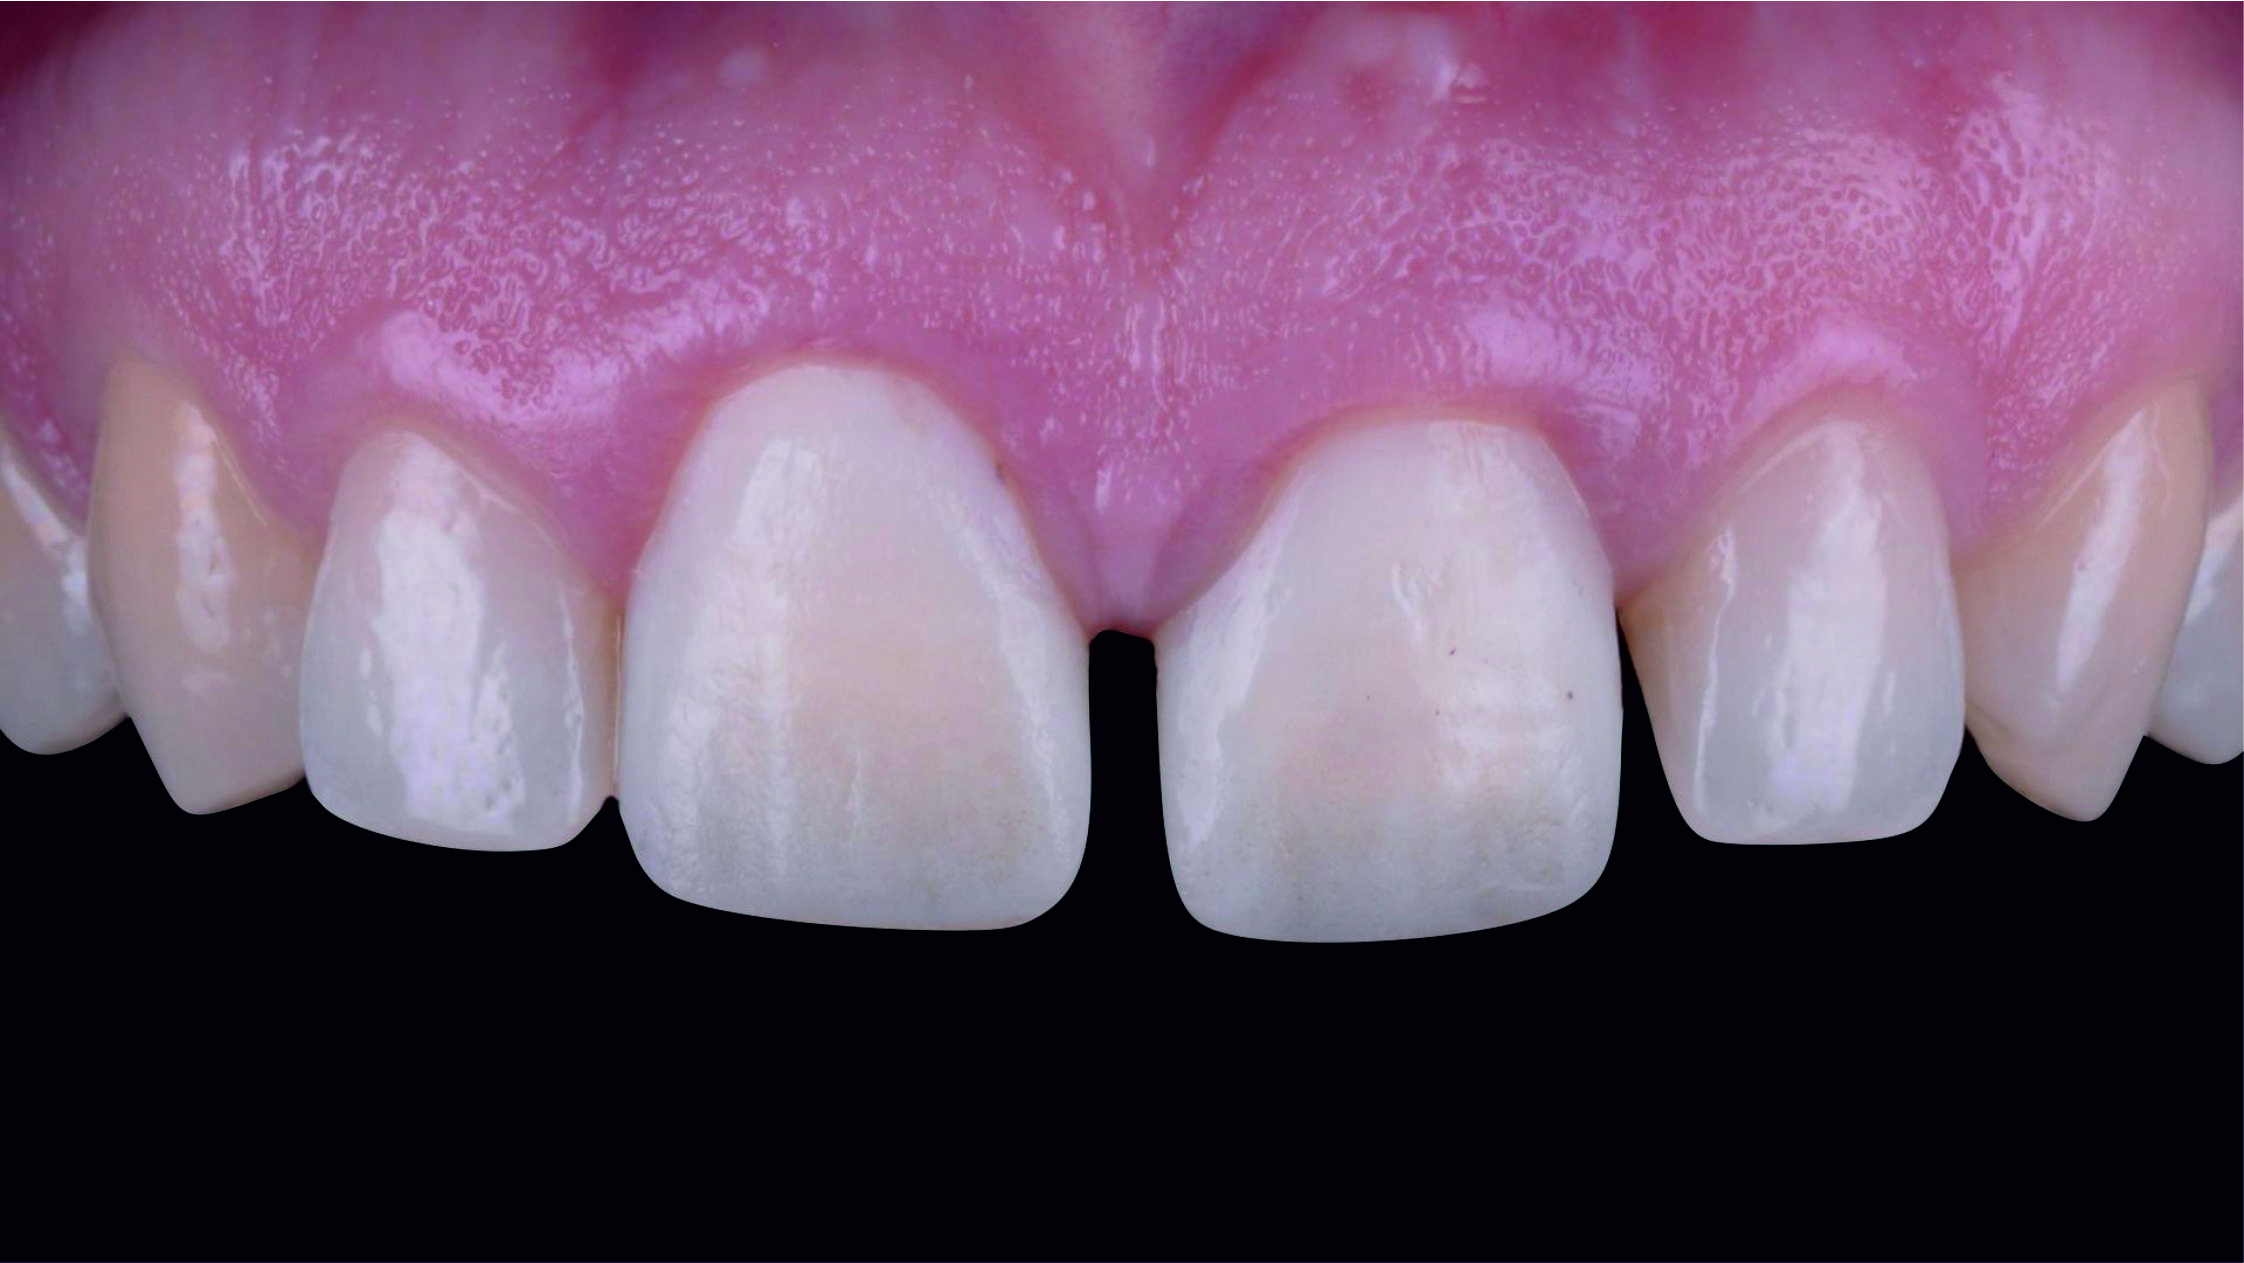

Фото 1. Початкова ситуація: жінка віком приблизно 35 років, із двома металокерамічними коронками, встановленими на верхніх центральних різцях.

Основні скарги: асиметрія центральних різців, запалення й кровоточивість ясен навколо коронок, загальне невдоволення естетикою цієї зони.